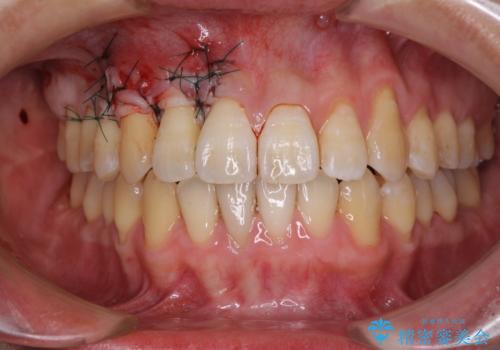

八重歯の歯根が見えている点も気になっているので、矯正歯科治療後に歯肉移植による根面被覆を行うこととしました。

矯正治療により元々気になっていた八重歯と、反対咬合が改善された歯の2本に対して根面被覆を行い、審美面の改善も達成しました。

- 外科手術のため、術後に痛みや腫れ、違和感を伴います

- 歯周組織再生治療は患者様の状態によって術後の経過が異なります(見た目が改善しない場合もあります)